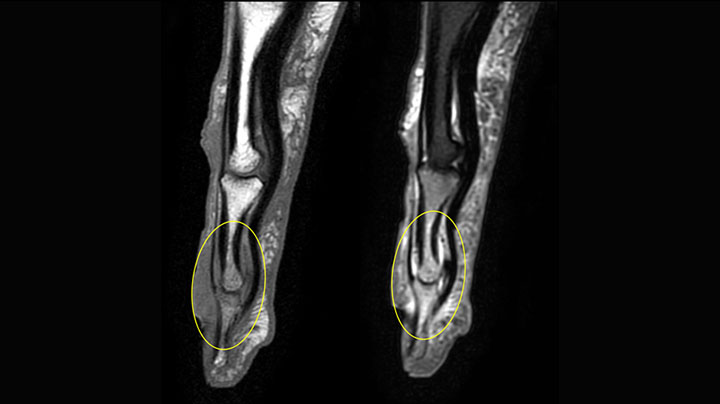

MRI examination on Prodiva 1.5T of a 72-year-old female with a malignant melanoma in the ankle. mDIXON TSE provides excellent fat suppression, without the distortion that is often seen at such extremities.

MRI of the finger with high SNR and good resolution in a 10 cm field of view on Prodiva 1.5T. The diagnosis in this 63-year-old patient is bone elasmanosis.